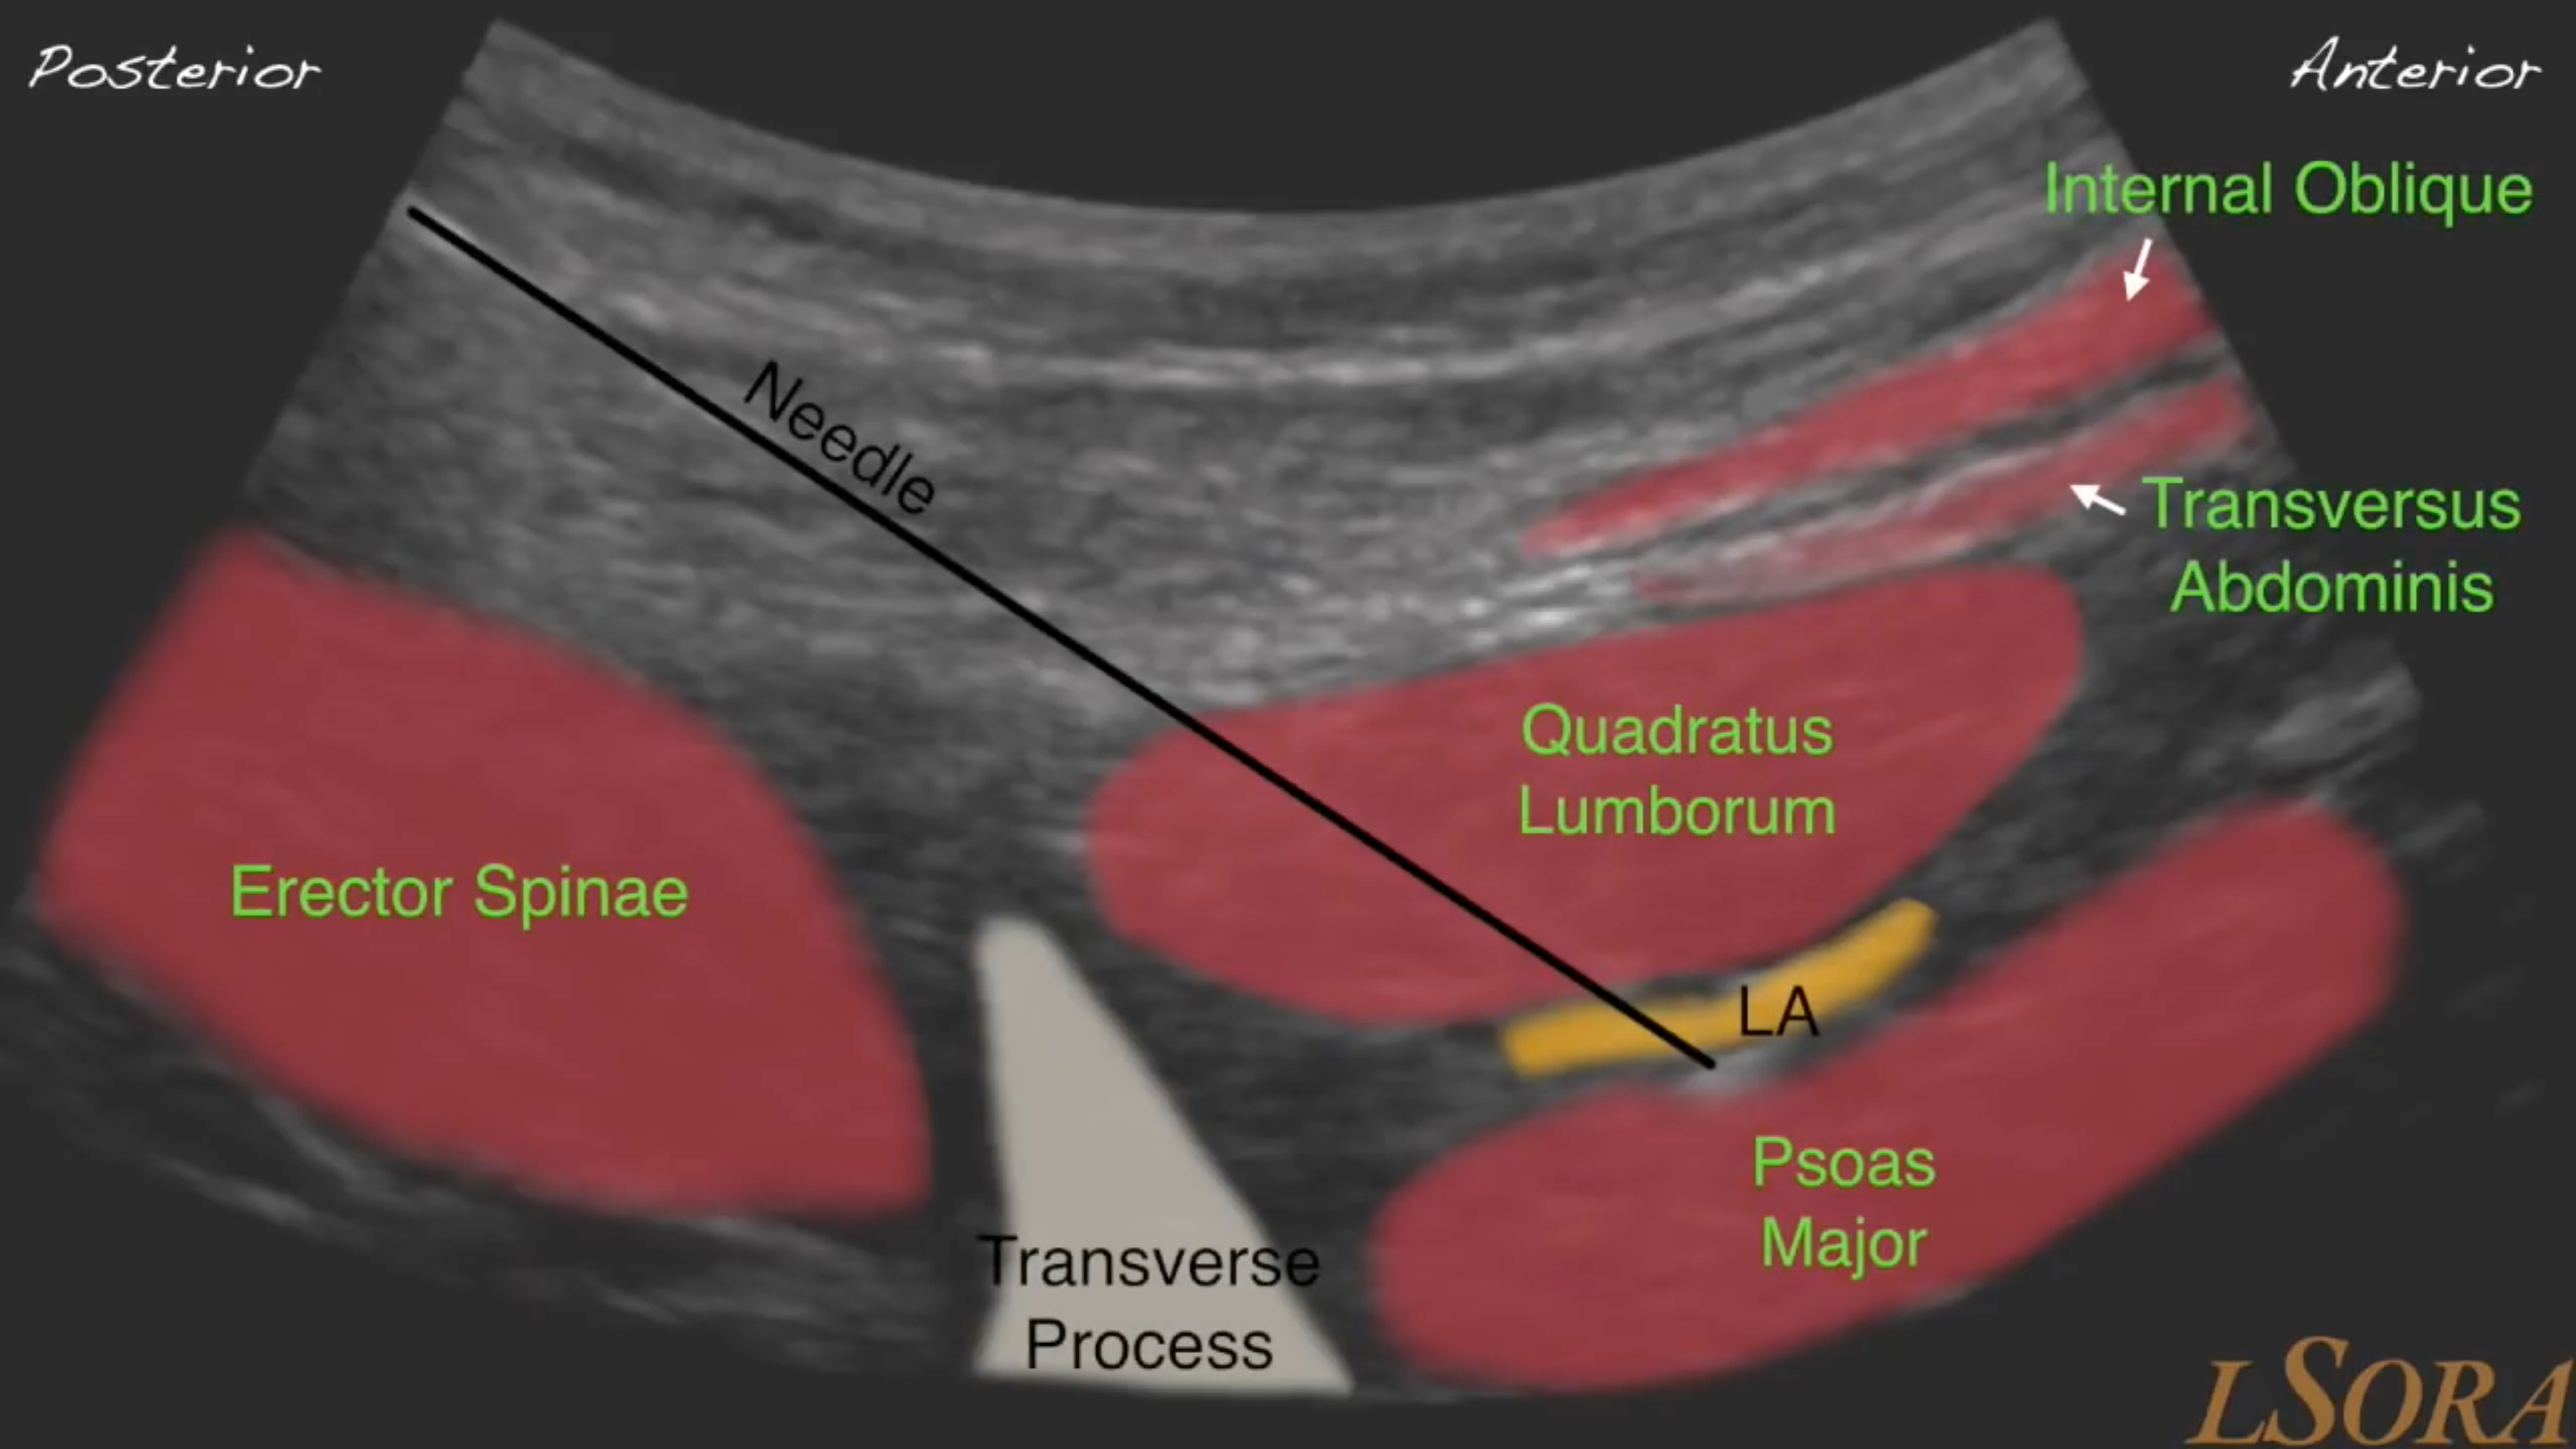

• LSORA Quadratus Lumborum Block

This video tutorial was created by Dr Parthipan Jegendirabose (PJ) - Consultant Anaesthetist at Colchester General Hospital, UK, and Dr Amit Pawa, and Dr Mark Ibrahim who are both Consultant Anaesthetists at Guy’s & St Thomas’ NHS Foundation Trust in London, UK. Dr Amit Pawa is also the Regional ...